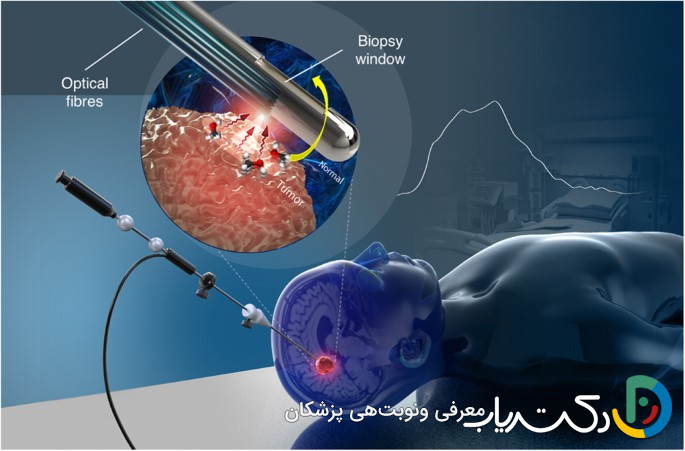

پس از آنکه یک توده در مغز از طریق روشهای تصویربرداری مانند MRI شناسایی شد، قدم بعدی برای تشخیص قطعی، نمونهبرداری از بافت تومور است. هرچند تصویربرداری میتواند اطلاعات ارزشمندی در مورد اندازه و مکان تومور بدهد، اما نمیتواند ماهیت سلولی آن را مشخص کند. این فرآیند که بیوپسی (Biopsy) نامیده میشود، سنگ بنای تعیین گرید تومور است.

نقش پاتولوژیست در تعیین گرید

نمونه بافت تومور که طی جراحی یا بیوپسی سوزنی (مانند بیوپسی استریوتاکتیک) برداشته شده، به آزمایشگاه پاتولوژی فرستاده میشود. در آنجا، یک پزشک متخصص به نام پاتولوژیست، که در تشخیص بیماریها از طریق بررسی بافتها تخصص دارد، فرآیندی دقیق را آغاز میکند. بافت ابتدا پردازش شده، در بلوکهای پارافینی قرار گرفته و سپس با دستگاهی به نام میکروتوم به لایههای بسیار نازک برش داده میشود. این لایهها روی اسلایدهای شیشهای قرار گرفته و با رنگهای مخصوصی (مانند رنگآمیزی H&E) رنگآمیزی میشوند تا ساختارهای سلولی زیر میکروسکوپ قابل مشاهده باشند.

۵. دقیقترین راه برای تعیین گرید تومور چیست؟ تنها راه قطعی و دقیق برای تعیین گرید تومور، تشخیص یکپارچه است. این به معنای ترکیب نتایج بررسی میکروسکوپی نمونه بافت (هیستوپاتولوژی) با آنالیز ویژگیهای مولکولی و ژنتیکی تومور است. این اطلاعات که از طریق بیوپسی یا جراحی به دست میآید، کاملترین تصویر از ماهیت تومور را ارائه میدهد.